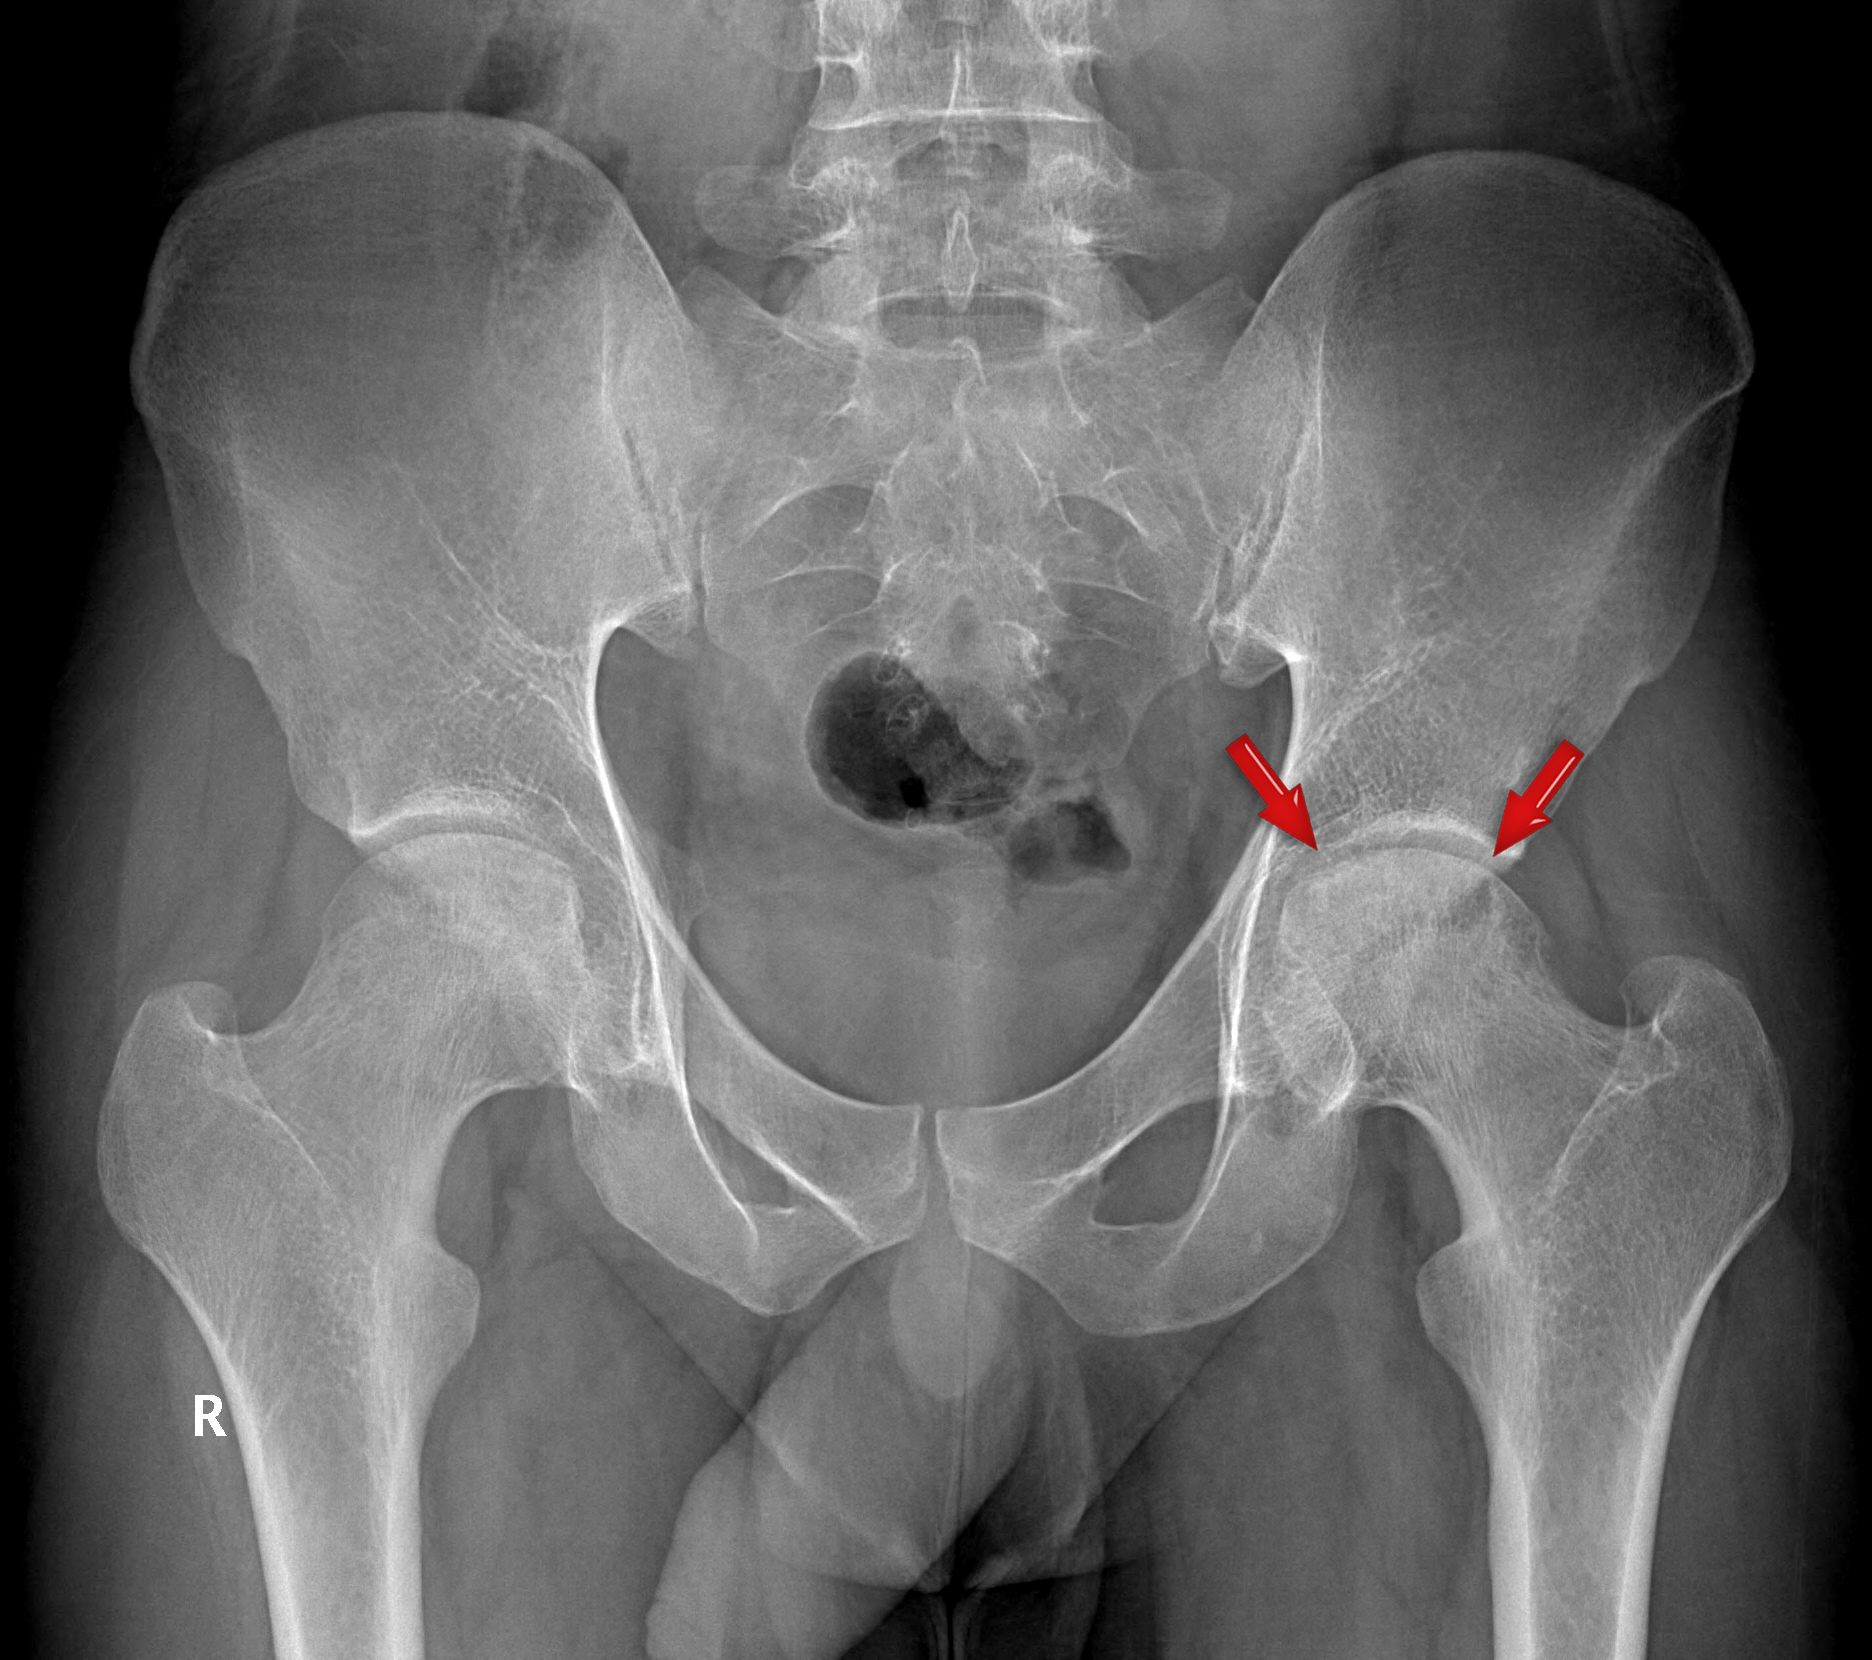

Avascular necrosis of the Hip Joint

Avascualar necrosis of the femoral head